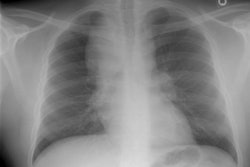

OBJECTIVE. We reviewed the imaging findings in nine patients with idiopathic giant bullous emphysema. This progressive condition is characterized by large bullae, usually seen in association with several forms of emphysema, and usually occurs in young men, most of whom are smokers. MATERIALS AND METHODS. Nine patients with chest radiographic evidence of a bulla or bullae occupying at least one third of a hemithorax, who had also been examined with high-resolution CT, were included in this retrospective study. We examined the size, distribution, and locations of bullae. On high-resolution CT scans, bullae were categorized as predominantly subpleural or intraparenchymal. RESULTS. In eight of the nine cases, the chest radiographs showed variable asymmetry in the distribution of bullae. Bullous disease involved predominantly the upper lobes. High-resolution CT showed bullae from 1 to 20 cm in diameter, but most were 2-8 cm in diameter. Paraseptal emphysema and subpleural bullae were the predominant findings in all nine patients. Seven patients had separate centrilobular emphysema of various degrees and intraparenchymal bullae. None of the intraparenchymal bullae were larger than 2-3 cm. Additionally, two non-small-cell lung cancers were seen in our series. CONCLUSION. The dominant and consistent feature seen on high-resolution CT scans in both smokers and nonsmokers is extensive paraseptal emphysema merging into giant bullae. Associated centrilobular emphysema, seen in cigarette smokers, is the important variable finding for determining the extent of underlying parenchymal disease, which may help in the preoperative assessment of giant bullous lung disease.